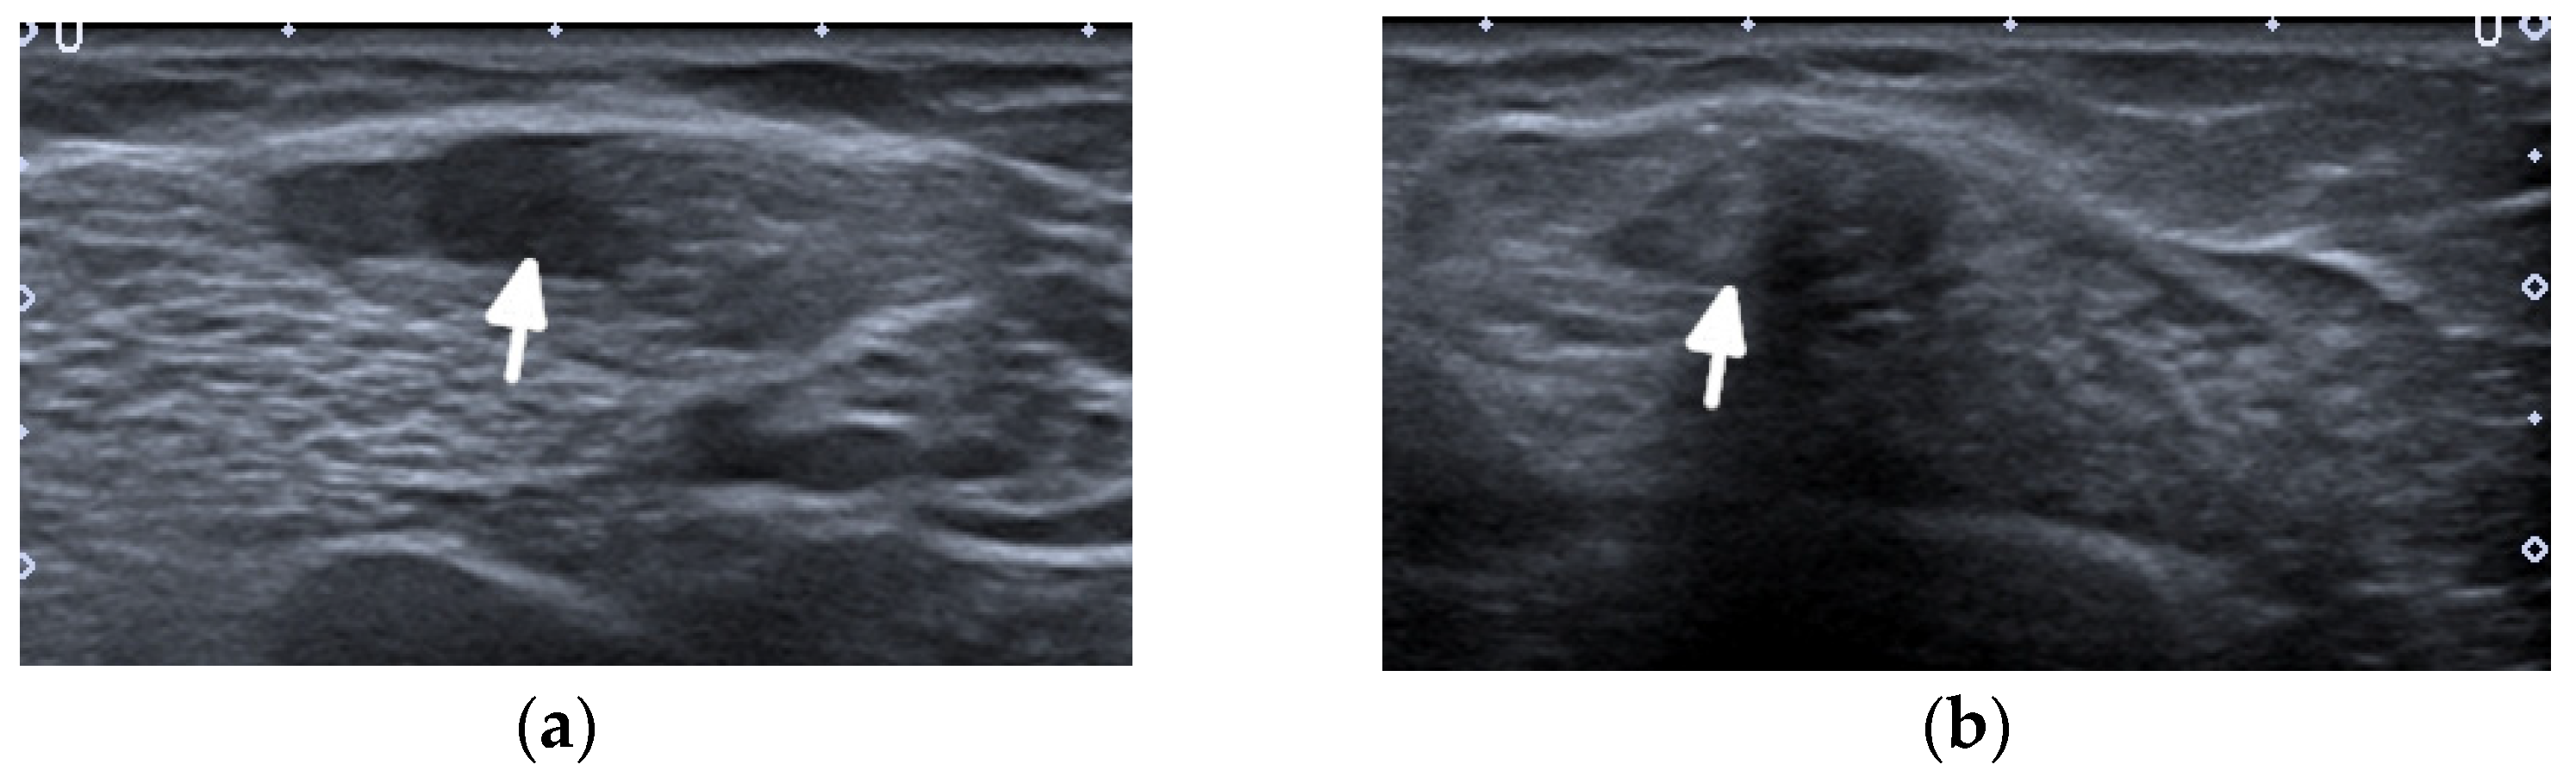

The imaging features of facial LP are extremely scarce in the literature (Figure 10).

Figure 10.

A 48-year-old female patient with systemic lupous erythematosus and a long history of lupus panniculitis and post-inflammatory atrophy of the subcutaneous tissues of the left cheek without active inflammation (arrow), seen in (a) the axial T2-weighted time spin echo and (b) T2 turbo inversion recovery magnitude MR images.

US will likely show inflammatory changes and hyperemia along the involved and surrounding subcutaneous adipose layer. However, the main role of US is to exclude an underlying abscess, drainable fluid collection, or mass.

If US is unrevealing, MRI is the imaging modality of choice. The hallmark of LP on MRI is the loss of the normal T1 bright signal within the subcutaneous adipose layer. In active stages, a high signal intensity is seen on the fluid-sensitive sequences with bright, hazy enhancement on the post contrast T1-weighted images with fat saturation. It is important to distinguish LP from lymphoma, which unlike LP, does not track along the fatty tissue planes.